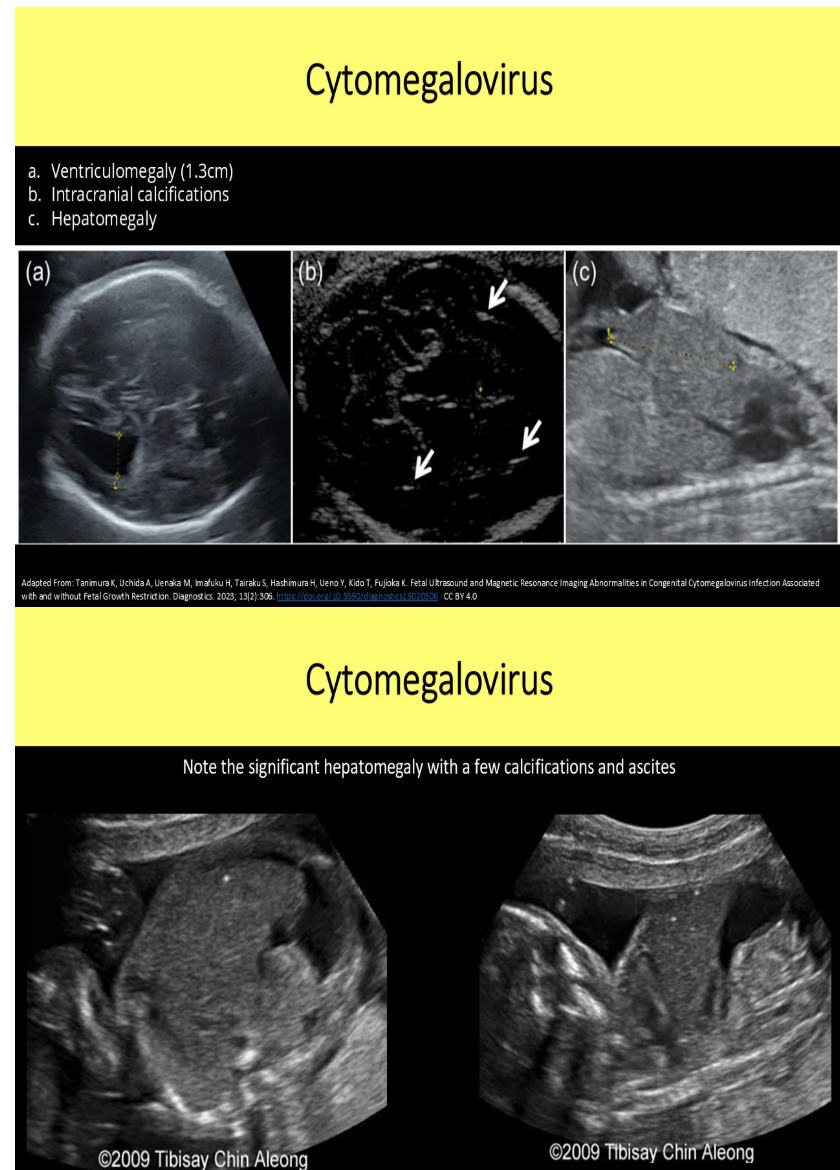

multiple small calcifications are seen in the fetal liver + brain. mild ventriculomegaly is also noted. which is the most likely cause

a) air in the fetal vessel

b) trisomy 13

c) cytomegalovirus infection

d) atherosclerosis in the fetal vessels

what is the most common cerebral finding w/cytomegalovirus

a) macrocephaly

b) cerebellar hyperplasia

c) exaggerated clefting of the cerebral tissue

d) hyperechoic periventricular halo + septations within occipital horns